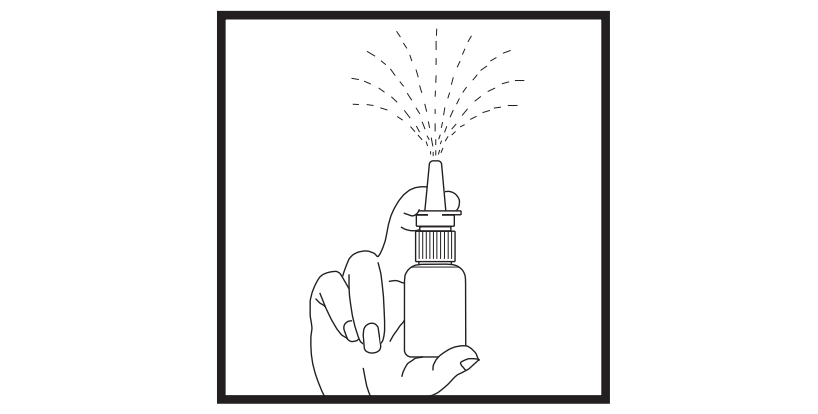

3. Hold the bottle in an upright position away from you. Apply pressure EVENLY to the

"shoulders" and push down QUICKLY AND FIRMLY until a fine spray occurs. Usually the

spray will appear after about 5 to 10 pumps.

Your pump should produce a fine mist, which can only be produced by a quick and firm

pumping action. It is normal to see some larger droplets of liquid within the fine

mist. However, if your Synarel comes out of the pump as a thin stream of liquid rather

than as a fine mist, it may not be as effective and you should return this spray to

your pharmacist.

DO NOT TRY TO ENLARGE THE TINY HOLE IN THE SPRAYER. If the hole is enlarged, the pump will deliver an improper dose of Synarel.

The pump is made to deliver only a set amount of medication, no matter how hard you

squeeze it.